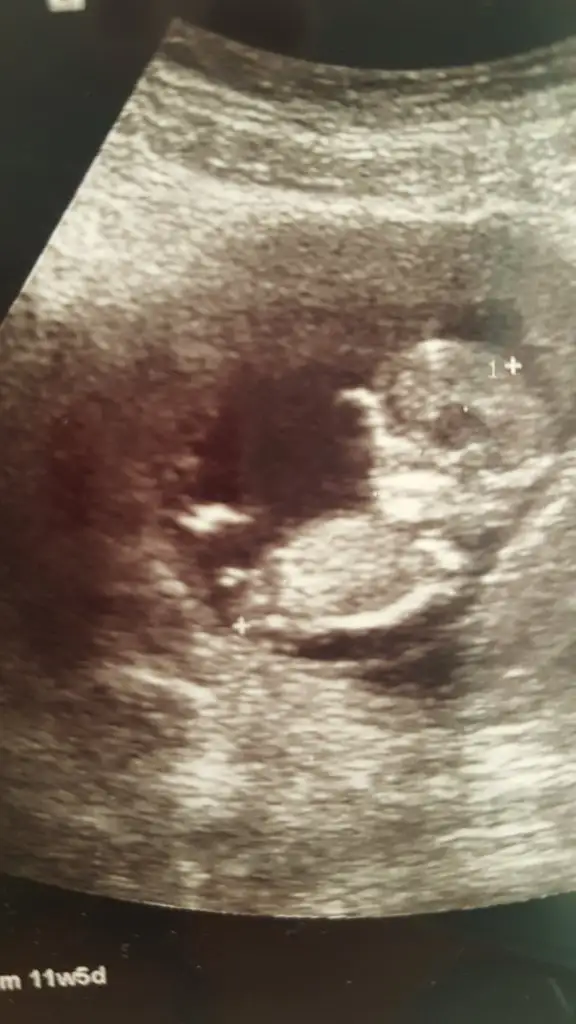

Kız diyorlarda en iyi nub 11 12 13 hafta USG paylasin

Önce erkek demişti Dr şimdi kız dedi sanırım yanıldıkErkek görünüyor

Aa sasirdim kaç haftalikta kız dediÖnce erkek demişti Dr şimdi kız dedi sanırım yanıldık

17 haftada kız dedi 14 te erkek demiştiAa sasirdim kaç haftalikta kız dedihayırlısı olsun cnm ilk bebismi

14 de küçük hafta değilmiş hayırlısı cnm detaylıca kadar alış veriş yapmayın bence bende 20+ da gittim kesinleşince alış veriş yaptım17 haftada kız dedi 14 te erkek demiştievet ilk bebiş Allah'ın izni ile

Bende öyle düşünüyorum hayırlısı inşallah14 de küçük hafta değilmiş hayırlısı cnm detaylıca kadar alış veriş yapmayın bence bende 20+ da gittim kesinleşince alış veriş yaptım

15+ da nub olmaz boş görünüyor sanki kız gibi 11 12 13 haftalar olmalı nub icin